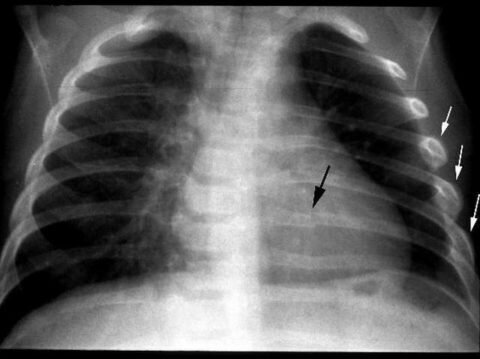

Затяжной болевой синдром, как в вашем случае, дает основание подозревать на наличие гипоксии, поскольку дыхание становится поверхностным и хронически не хватает воздуха. Если ребра повреждены на уровне легких, может развиваться пневмония, пневмоторакс (скопление воздуха в плевральной полости) и гидроторакс (скопление жидкости в плевральной полости). Может начаться длительный стресс.

Если вам не было назначено лечение, то нужно провести повторную диагностику помощью рентгена КТ, МРТ и адекватное лечение по результатам исследования.